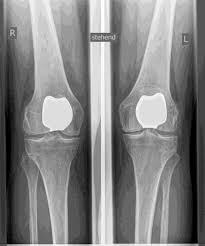

PRÓTESIS DESLIZANTE

El reemplazo parcial de la articulación de la rodilla es posible en todas las áreas de la articulación, pero con mayor frecuencia se realiza en el interior de la articulación de la rodilla y, a menudo, se denomina coloquialmente prótesis de trineo. Al igual que en la dentadura postiza completa, el cartílago defectuoso se reemplaza con una nueva superficie y se inserta una incrustación de plástico en el medio. Para una prótesis parcial, todas las estructuras ligamentosas, especialmente los ligamentos cruzados, deben estar prácticamente intactas.